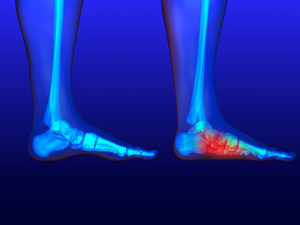

The general cause of a condition referred to as gout is an excess of uric acid that accumulates in the body. The big toe is typically affected, and obvious symptoms may include intense pain, swelling, and redness in the surrounding areas. It will often appear as an inflamed protrusion on the side of the big toe, and may affect the ability to walk. Research has shown that it may be a controllable condition and may occur because of the foods that are ingested. There may be several items that may fall into this category, including the consumption of red meat, an excessive salty foods, and any type of shellfish. Drinking excess alcohol may also lead to the development of gout, in addition to a family history of high blood pressure. Occasionally, there may be specific medical conditions in which the body has difficulty eliminating uric acid, such as kidney or thyroid ailments. The treatment for gout can vary, so it’s advised to consult with a podiatrist for a proper diagnosis.

The general cause of a condition referred to as gout is an excess of uric acid that accumulates in the body. The big toe is typically affected, and obvious symptoms may include intense pain, swelling, and redness in the surrounding areas. It will often appear as an inflamed protrusion on the side of the big toe, and may affect the ability to walk. Research has shown that it may be a controllable condition and may occur because of the foods that are ingested. There may be several items that may fall into this category, including the consumption of red meat, an excessive salty foods, and any type of shellfish. Drinking excess alcohol may also lead to the development of gout, in addition to a family history of high blood pressure. Occasionally, there may be specific medical conditions in which the body has difficulty eliminating uric acid, such as kidney or thyroid ailments. The treatment for gout can vary, so it’s advised to consult with a podiatrist for a proper diagnosis.

Gout is a form of arthritis that is characterized by sudden, severe attacks of pain, redness, and tenderness in the joints. The condition usually affects the joint at the base of the big toe. A gout attack can occur at any random time, such as the middle of the night while you are asleep.

Gout – is caused by an excess of uric acid in the body. Common symptoms include pain, inflammation, and redness at the metatarsal/phalangeal joint of the base big toe. Gout can be treated by NSAIDs to relieve pain and inflammation, and other drugs that lower the acid levels in the body.